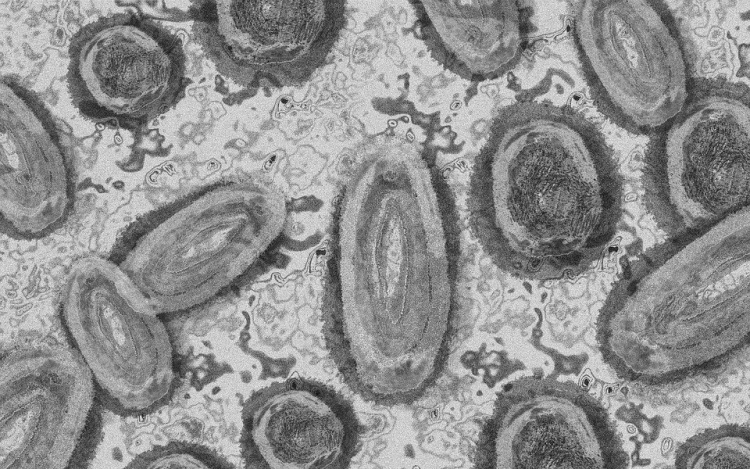

Meghaladta a 13 ezret a majomhimlő-fertőzöttek száma az Egyesült Államokban, a legtöbb esetet Kaliforniában és New York államban regisztrálták.

Az amerikai járványügyi és betegségmegelőzési központ (CDC) szerdán közölt friss tanulmánya szerint a járvány ugyan elsősorban szexuális érintkezés útján terjed, de a fertőzöttek egy része tömegrendezvényeken kapta meg a vírust. A hivatal arra hívja fel a figyelmet, hogy a majomhimlővel bárki megfertőződhet, ha másokkal közeli testi kapcsolatba kerül, akár bőrfelületek érintkezése révén.

A legutóbbi adatok szerint 13 500 fölött van az igazolt fertőzöttek száma, az esetek csaknem felét Kalifornia, New York és Florida államokban regisztrálták.